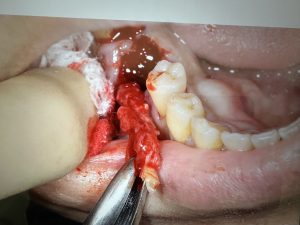

不良肉芽が凄かった方

プラットフォームスイッチングのお陰